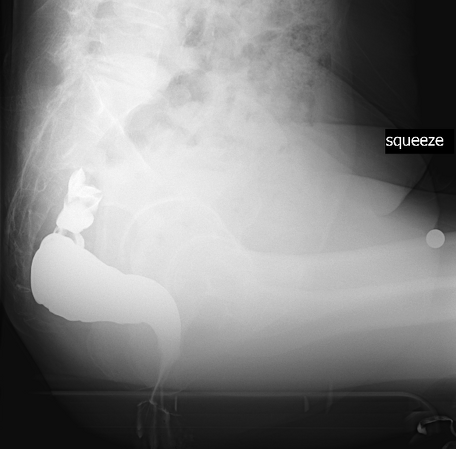

排便造影検査(ディフェコグラフィー)

お尻から擬似便(バリウムと小麦粉で作った物)を注入し、擬似便を排出する時の直腸肛門の動きをX線(レントゲン)で確認します。

主に排便時の直腸肛門の動きや形態の変化、直腸瘤の有無を評価します。